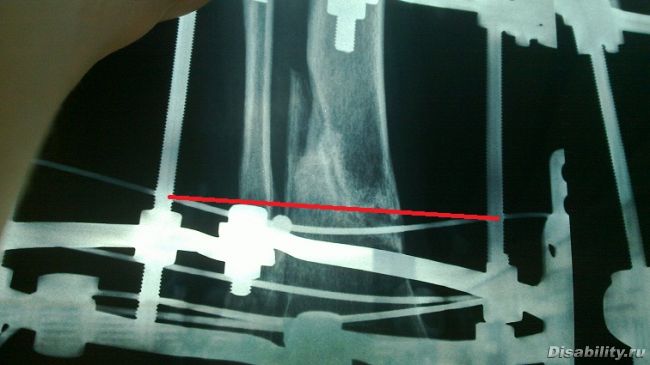

Снимки через 3, 15 и 20 недель после операции.

Снимки через 15 - передержанные, поэтому кажется, что 5 недель спустя

стало хуже.

Фронтальный 20-недельный - самый информативный - перевернут вверх

ногами. Там видно, что косой осколок на основной оси кости не прирос

толком, и поэтому нельзя снять аппарат - при попытке на него

наступить он вылетит вбок. Сейчас у меня есть 22-недельный снимок,

на котором эта косая щель по основной оси уже закрывается.

Если 21-го, когда пойду в очередной раз, она совсем закроется -

тогда есть шанс. Правда, я уже особо не надеюсь.